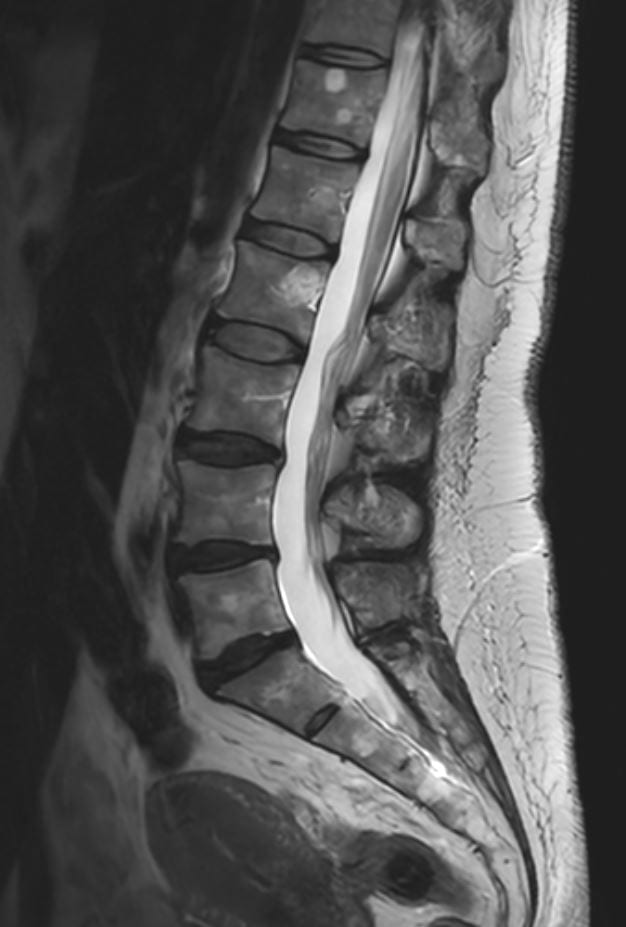

Få præcis diagnose af dine SI-ledsmerter med avanceret MR-scanning hos Progardia. Vores kraftfulde 3 tesla scanner giver ekstraordinært detaljerede billeder af sacroiliacaleddet, hvor rygsøjlen møder bækkenet. Oplev markedets mest nøjagtige visualisering af inflammation, artrit og andre forandringer, der ofte overses ved konventionelle undersøgelser.

En MR-scanning af SI-led (sacroiliacaled) er en avanceret, smertefri undersøgelse, der giver detaljerede billeder af forbindelsen mellem korsbenet (sacrum) og hoftebenet (ilium).

Vores 3 tesla MR-scanner bruger et kraftigt magnetfelt og radiobølger til at skabe præcise billeder af leddet, omkringliggende knogler, brusk, ledbånd og bløddele – helt uden brug af røntgenstråling.

SI-leddet er et komplekst led, der ofte er svært at undersøge med konventionelle metoder. MR-scanning kan vise tidlige tegn på inflammation, artrit, slidgigt og andre forandringer, der kan være årsag til lænde-, hofte- eller bækkensmerter. Denne undersøgelse er særligt værdifuld ved mistanke om inflammatoriske rygsygdomme som f.eks. ankyloserende spondylitis (Morbus Bechterew).

Eksempler på MR Scanninger